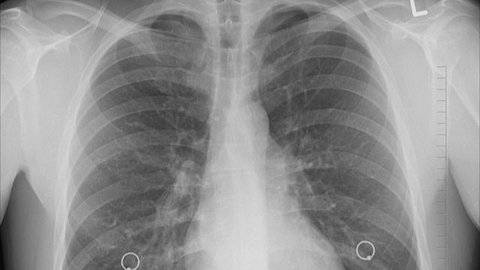

Sering Dianggap Sama, Ini Sebenarnya Perbedaan Pneumonia dan Paru-paru Basah

Pneumonia dan paru-paru basah sering dianggap sebagai kondisi yang sama padahal terdapat perbedaan di antara keduanya.

Pneumonia Disebabkan Mandi Malam Hari, Mitos atau Fakta?

Pneumonia merupakan radang atau infeksi pada jaringan paru.

Apakah Mandi Malam Menyebabkan Paru-Paru Basah? Ketahui Fakta dan Penjelasannya

Kepercayaan ini sudah lama beredar di masyarakat. Hal ini membuat banyak orang enggan mandi malam karena takut terkena penyakit.

Tidur di Lantai Bukan Pemicu Paru-paru Basah, Ini Penyebab Sebenarnya

Selama ini, banyak orang percaya bahwa paru-paru basah terjadi akibat kebiasaan tidur di lantai. Namun ternyata faktanya tidak seperti itu.

Mitos atau Fakta, Kipas Angin Penyebab Paru-paru Basah?

Benarkah kipas angin dapat menjadi penyebab paru-paru basah? Berikut jawabannya.

Gejala Paru-Paru Basah yang Mudah Dikenali, Jangan Sepelekan Penyebabnya

Penundaan dalam perawatan bisa berakibat serius, bahkan mengancam nyawa.